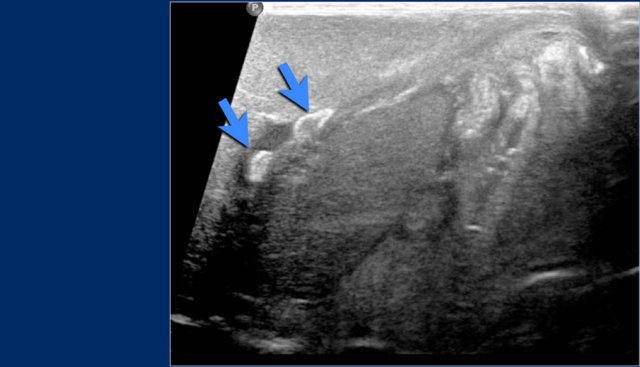

Umbilical venous line (7 )

Study the images.

Then continue reading.

The findings are:

• The umbilical venous line is too deep.

The line probably went through a patent foramen ovale and through the left atrium into a pulmonary vein.

In this patient ultrasound detected a thrombus in the left portal vein after umbilical venous line (arrows).

Catheter malposition in the left portal vein increases the occurrence of portal venous thrombosis.

Clinically silent portal venous thrombosis is frequently associated with catheterization of the umbilical vein in critically ill neonates, and spontaneous resolution without any treatment is expected in many cases.